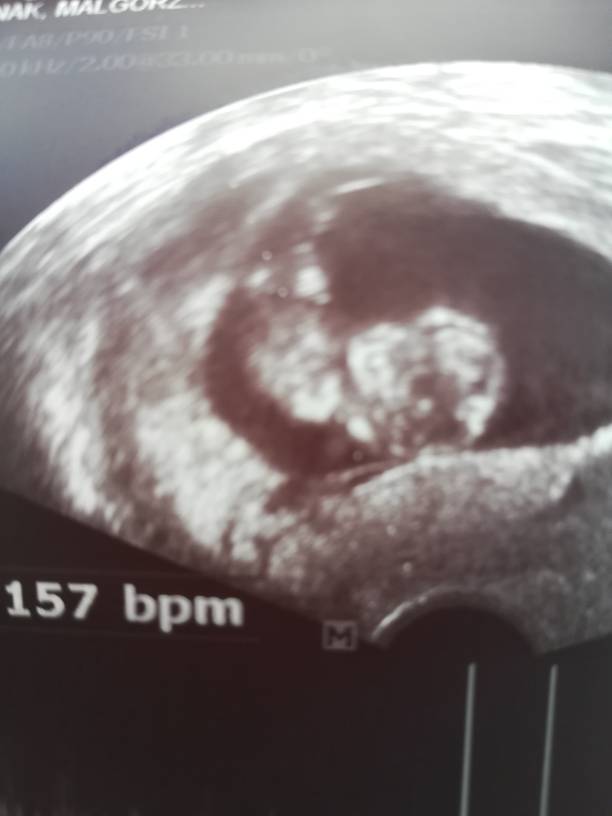

Gratulacje :*Ja już po wizycie, maleństwo ma 4,17 cm, serducho bije 157 razy na minutę [emoji7] [emoji7] [emoji7] Zobacz załącznik 871100